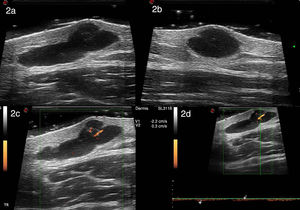

Se realizó una EDAR con una sonda de 22MHz (MyLab Class C, Esaote) que mostró una imagen anecoica bien delimitada localizada en la dermis y la hipodermis, de forma redondeada en el eje longitudinal y polilobulada en el eje transversal, con un septo en su interior, que medía 11,9mm en el eje transversal, 5,9mm en el eje longitudinal y 4,2mm de espesor. La lesión presentaba refuerzo posterior. El modo power Doppler evidenció escasa vascularización intralesional, con vasos venosos y arteriales de baja velocidad que medían entre 0,2 y 0,4mm de diámetro; en el Doppler espectral los vasos arteriales presentaban un pico sistólico máximo de 2,2cm/seg (fig. 2). Por las características ecográficas se sospechó un tumor subcutáneo benigno o un hematoma. Sin embargo, debido al tiempo de evolución y sintomatología del paciente se procedió a la delimitación ecográfica de los márgenes tumorales y se extirpó quirúrgicamente.

Ecografía de alta resolución con sonda de 22MHz (MyLab class C, Esaote): imagen bien delimitada anecogénica polilobulada, con un septo en su interior, localizada en la dermis y la hipodermis que presenta refuerzo posterior y mide 11,9mm de diámetro transversal (a) y 5,9mm de diámetro longitudinal (b). Con power Doppler se evidencia escasa vascularización intralesional con vasos arteriales y venosos que miden entre 0,2 a 0,4mm de espesor (c). En el Doppler espectral los vasos arteriales presentaban un pico sistólico máximo de 2,2 cm/seg (d).